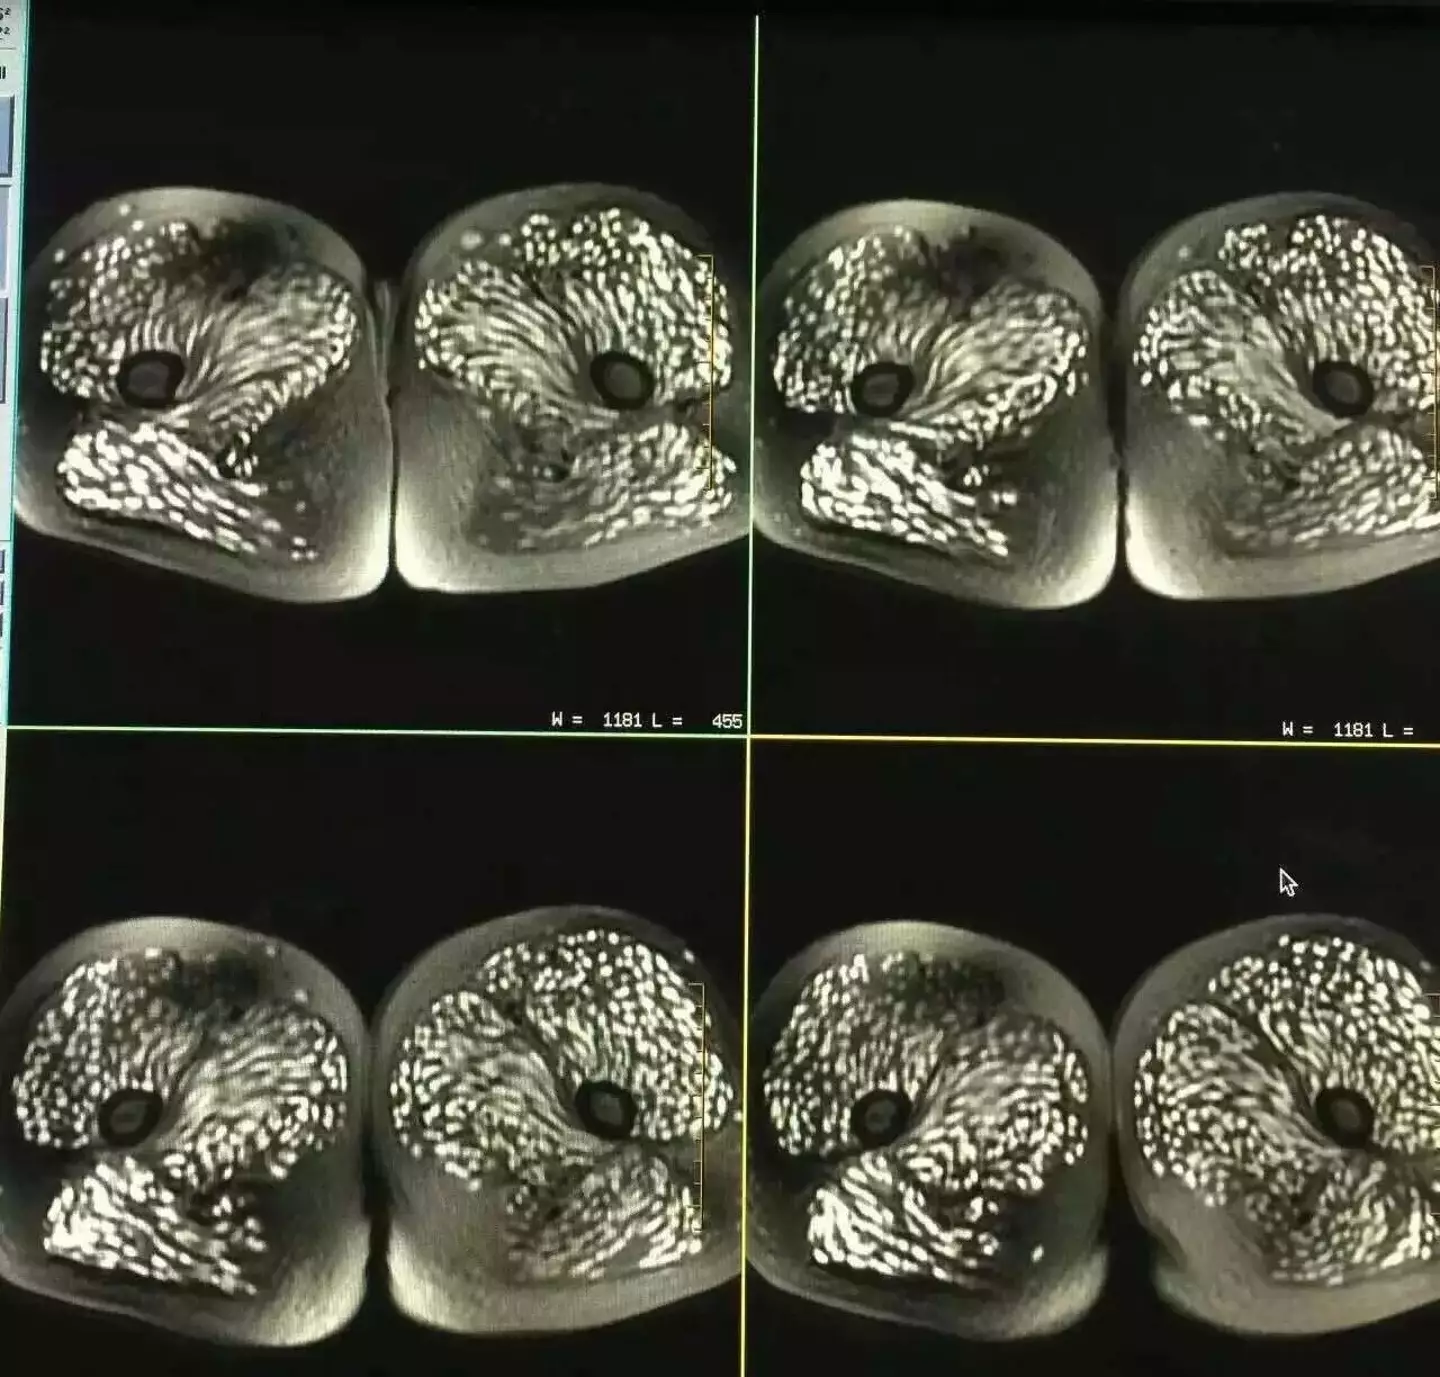

Disturbing scans have revealed the shocking consequences of a woman’s decade-long habit of eating raw pork, leaving her body riddled with parasites. The 23-year-old woman, referred to as Tingting (a pseudonym), from Yubeng Village in Deqin County, China, had been experiencing severe headaches, pain in her thighs, and discomfort in her eyes.

Concerned, she sought medical help in 2016, and the results of her MRI and CT scans were nothing short of horrifying.

Doctors were alarmed to discover that Tingting's body was infested with microscopic parasites, a result of cysticercosis—an infection caused by ingesting tapeworm eggs. These parasites had infiltrated her back muscles, abdomen, eyes, and even her brain.

The scans showed that the parasites were widespread, causing significant damage to her body. Her condition was further complicated by bulging eyes, retinal hemorrhage, multiple infections, and epileptic seizures, according to Professor Meng Qiang, chief physician of the Department of Neurology at the Provincial First Hospital.

The X-ray images of Tingting's parasite-infested body have sparked widespread disgust and concern online.